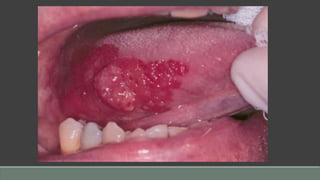

Erythroplakia

Clinical Presentation

• Red, often velvety, well-defined patch(es)

• Most common on floor of mouth, retromolar trigone area, lateral tongue

• Usually asymptomatic

• May be smooth to nodular

• Chiefly in males